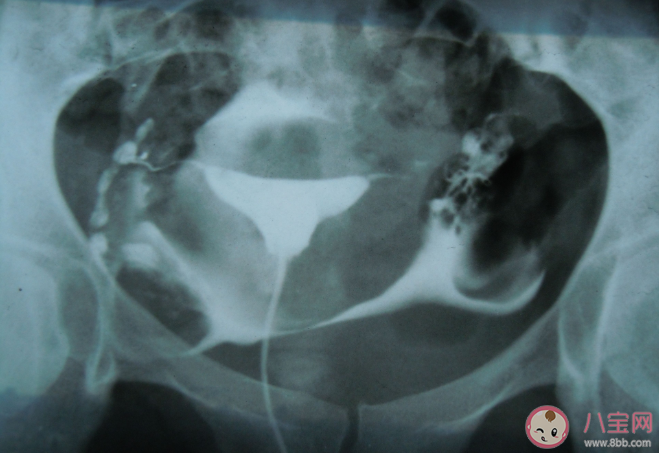

通過輸卵管造影發現輸卵管情況較為良好(比如通而不暢)或者患者本人對手術嚴重抗拒的,醫生會建議通過消炎、理療、活血化瘀等方法進行保守治療。

通過宮腹腔鏡手術分離粘連的部位,并在腹腔內注入防止粘連的藥物,術中通過判斷輸卵管管壁是否柔軟、管腔是否通暢、傘端粘膜是否完整、輸卵管周圍是否粘連這四個方面綜合評估輸卵管功能,并給出評分來指導后續治療和選擇妊娠方式(自然生育或者采用輔助生殖技術)。